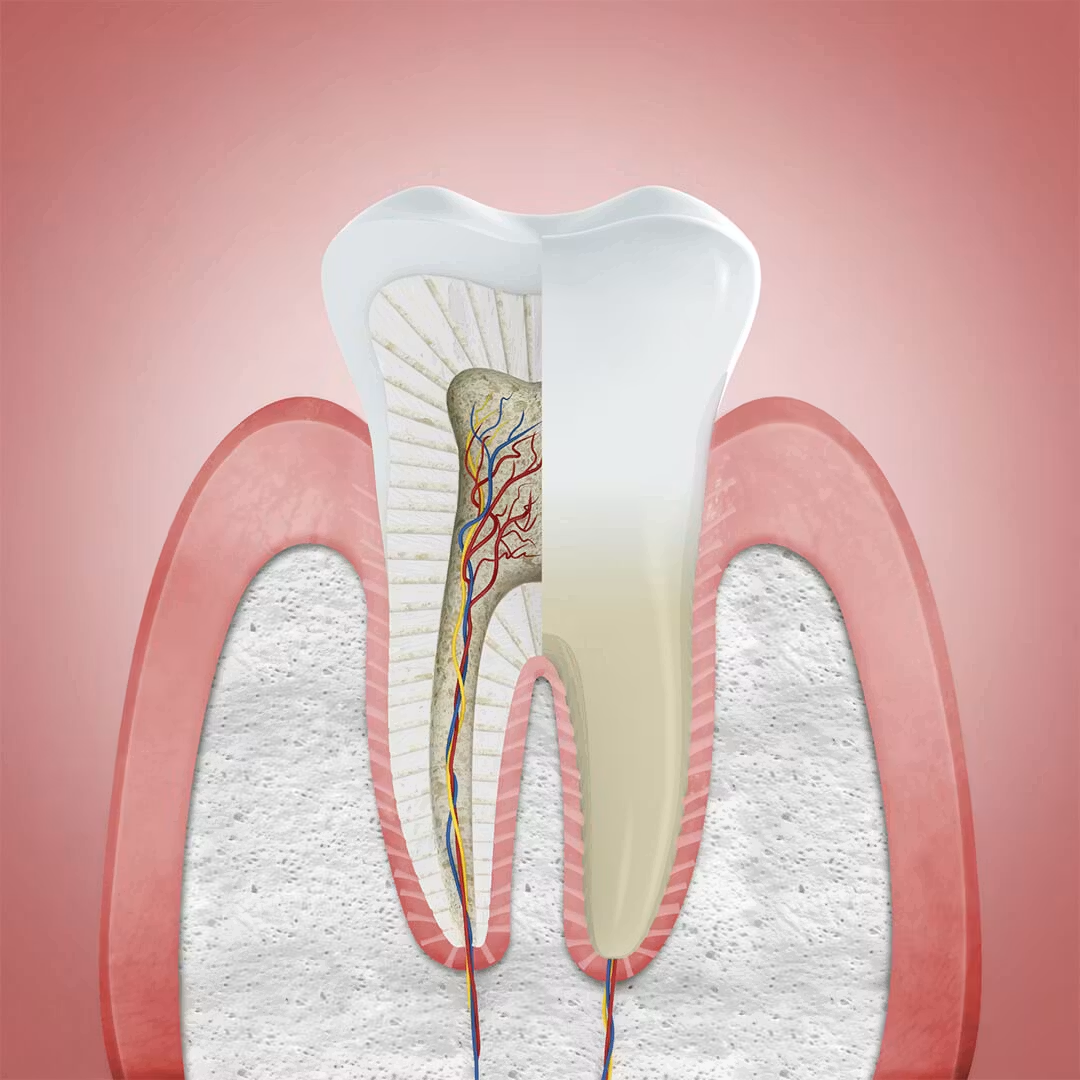

O que é Periodontia

A especialidade que protege o que sustenta seus dentes.

A Periodontia é a especialidade odontológica que cuida de todas as estruturas de sustentação dos dentes: gengiva, osso alveolar, cemento radicular e ligamento periodontal. Em resumo: é a especialidade que mantém seus dentes onde eles devem estar.